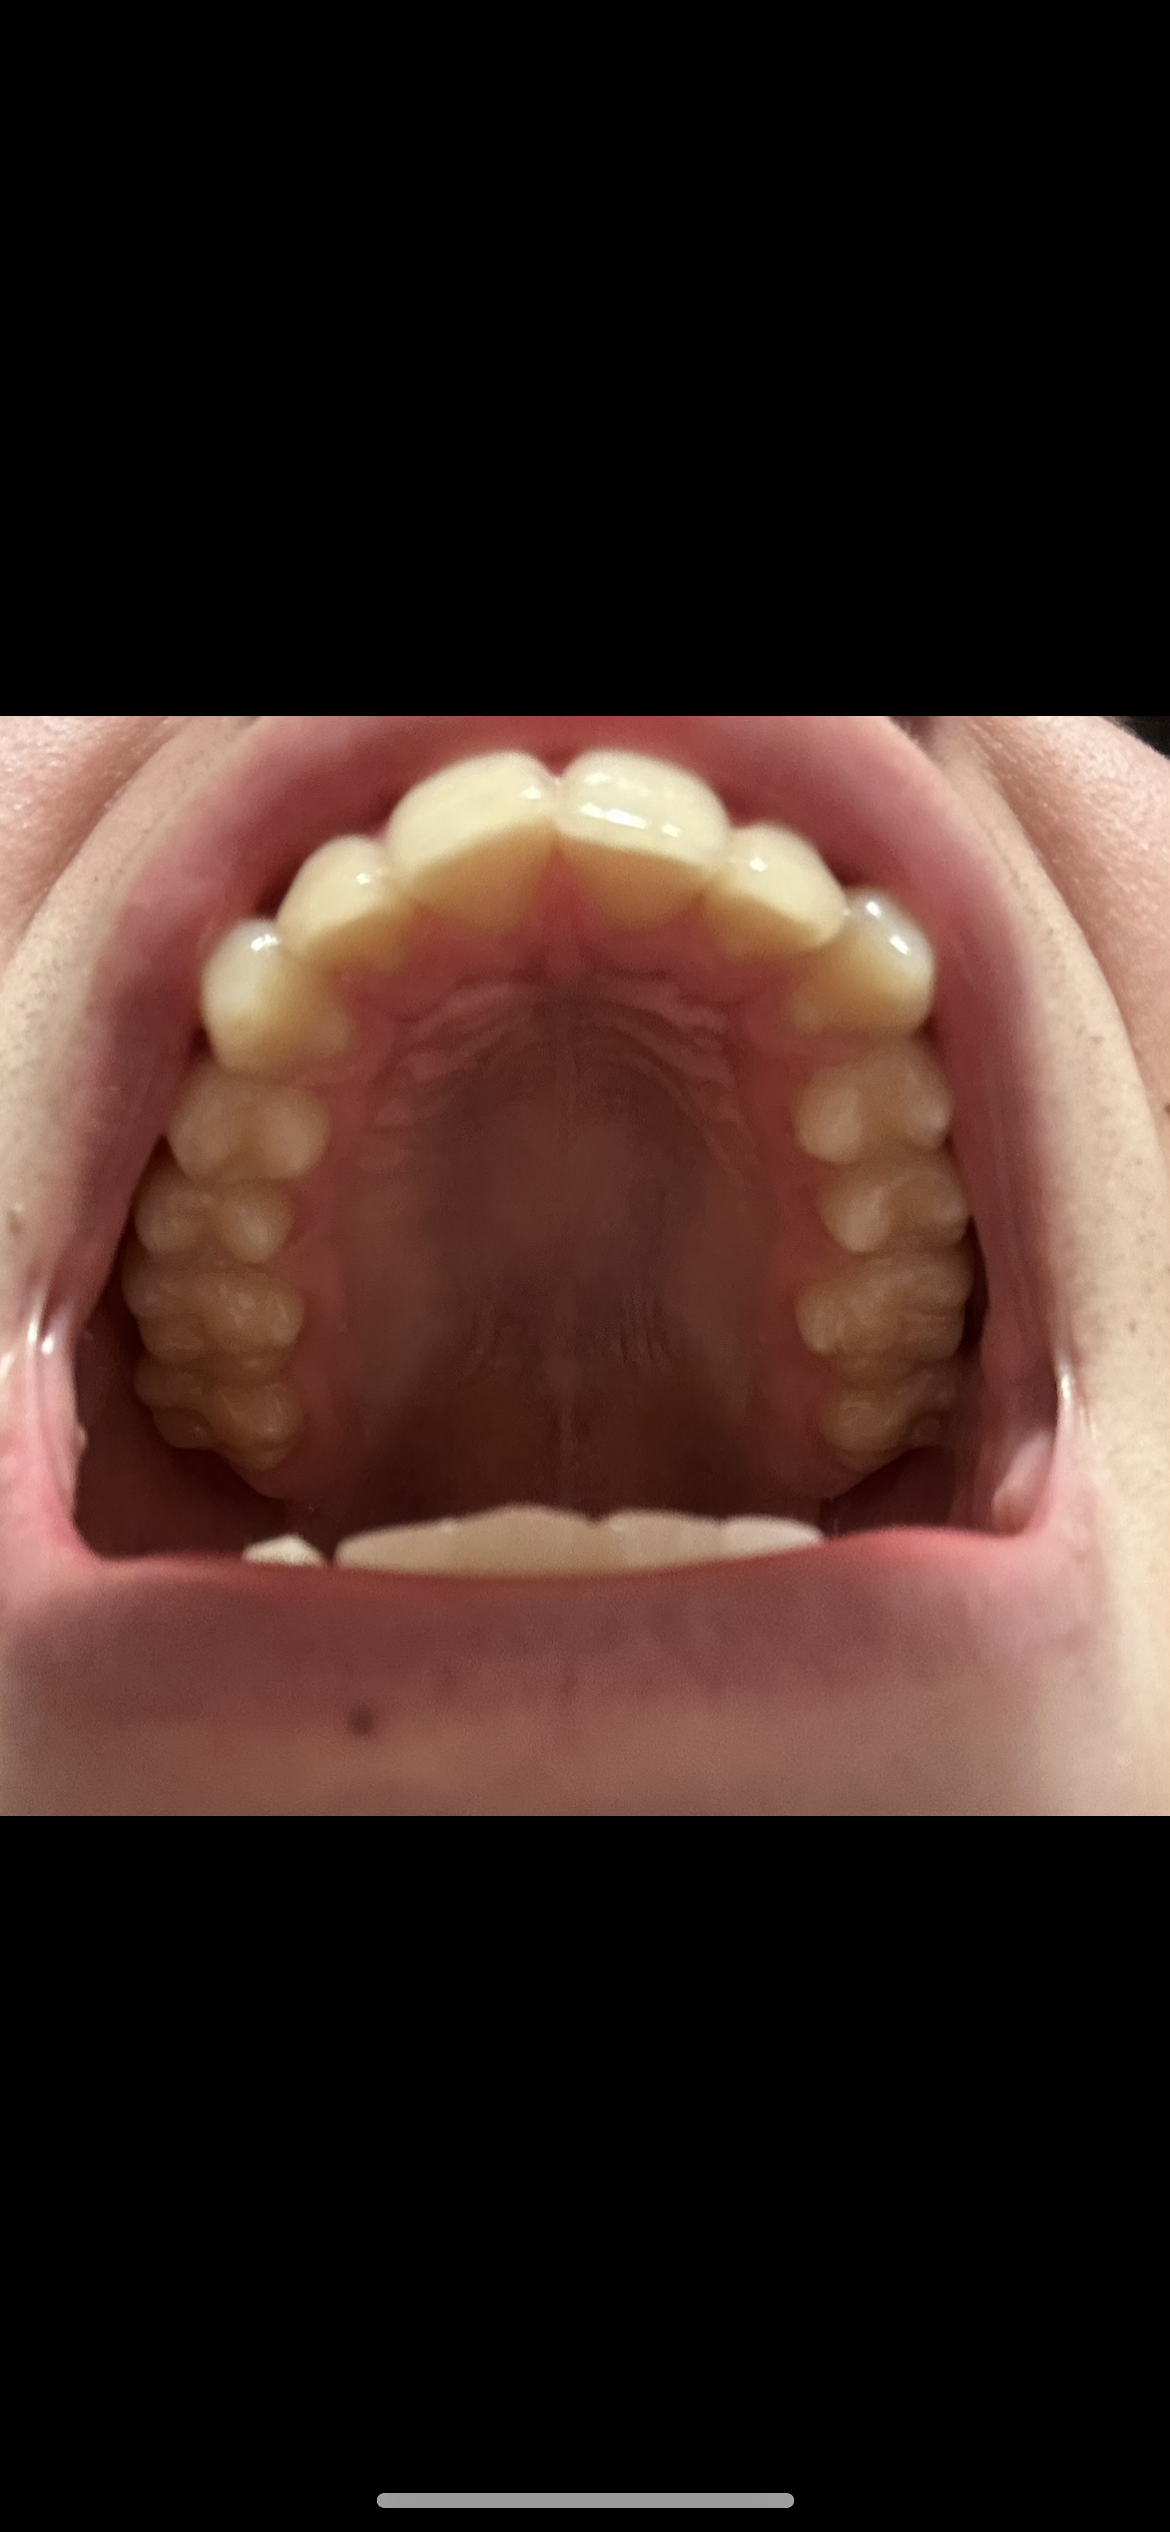

I think I hit a few of the criteria.

bad class 2, Okayish gonion width without needing implants and the sfs 0 gingival and upper incisor show smile.

Before I had camouflage orthodontics, I had textbook SFS indicators, like very little teet/gum show when smiling, collapsed looking chin, with deep mentolabial fold etc.

But since getting braces, all of these have been masked, now I’m getting decomp, they will all come back again before jaw surgery.

Yrah i dont see many of my teeth when I open my mouth like u said, maybe a small downgraft would help

you should see like 2-3 mm of teeth when doing this while being relaxed in the upper lip, Open slightly less then in this pic

Fuck I have almost no teeth show